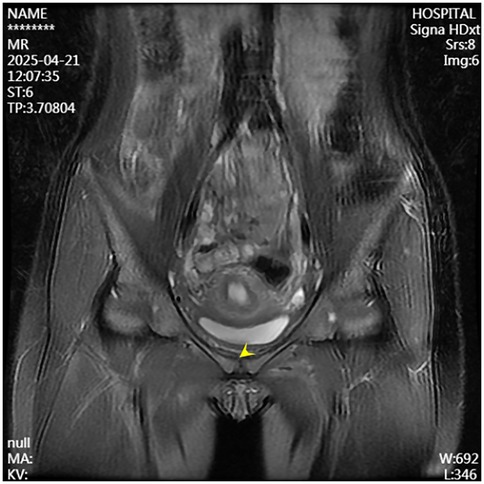

A 13-year-old female presented to the Department of Pediatrics at Dongguan Maternal and Child Health Hospital with a 10-day history of intermittent fever and pain in the pubic symphysis region. The patient denied a history of pelvic surgery, local trauma, or strenuous exercise. Her past medical and family histories were unremarkable. Between February 10 and 18, 2025, she was hospitalized at an external institution due to pubic symphysis pain, restricted lower limb mobility, and high fever. Blood cultures identified the presence of methicillin-resistant Staphylococcus aureus (MRSA) and she was treated initially with cephalosporins and penicillins which resolved the fever but only partially alleviated the pubic pain. Upon transfer to our hospital, physical examination revealed stable vital signs, no fever, localized tenderness and swelling over the pubic symphysis without erythema or fluctuance, bilateral restricted hip motion (aggravated by adduction and abduction), and an antalgic gait. The laboratory findings included a white blood cell count of 6.08 × 109/L (neutrophils: 64.0%), procalcitonin <0.1 ng/ml, and an erythrocyte sedimentation rate (ESR) of 80 mm/h. Blood cultures confirmed the presence of MRSA. Although intravenous antibiotics had resolved the fever, pubic pain and mobility limitations persisted, particularly with limited hip mobility, notably painful external rotation and adduction, where external rotation was less than 15 degrees and adduction was less than 10 degrees. Consultation with orthopedic specialists led to the suspicion of pubic symphysis infection, prompting an MRI examination. The imaging revealed infection of the pubic symphysis with bilateral osteomyelitis and a small abscess in the posteroinferior muscle layer (Figures 1, 2). Based on these clinical manifestations, laboratory results, and imaging findings, the diagnosis was confirmed as pubic symphysis infection with bilateral osteomyelitis and abscess formation.

Figure 1. Preoperative MRI indicates infection of the pubic symphysis.

Figure 2. Preoperative MRI shows infection at the pubic symphysis.